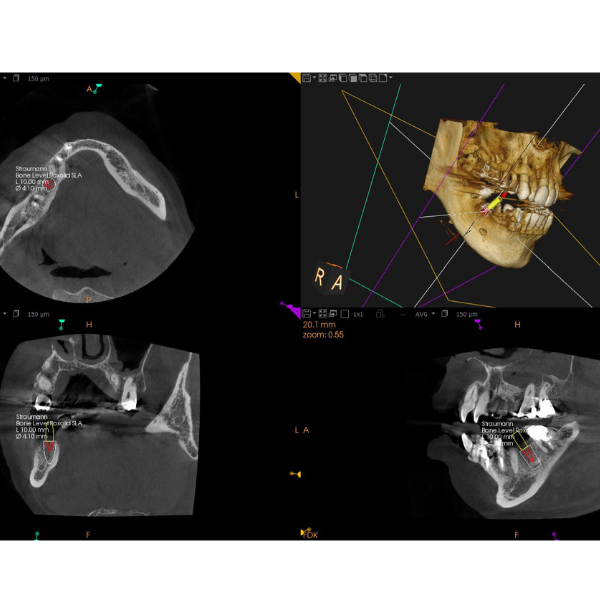

CT

手術の安全性と精度を高めるため、当院ではCTスキャンを活用しています。インプラント治療は、人工の歯根(インプラント体)をあごの骨に埋め込む治療です。あごの骨には神経や血管が通っているため、これらを傷つけないよう慎重な計画が必要です。

CTスキャンは、一般的な二次元レントゲンとは異なり、骨の構造を三次元で確認できるため、あごの骨内の神経や血管の正確な位置を把握することが可能です。これにより、より正確で安全な治療計画を立てることができます。